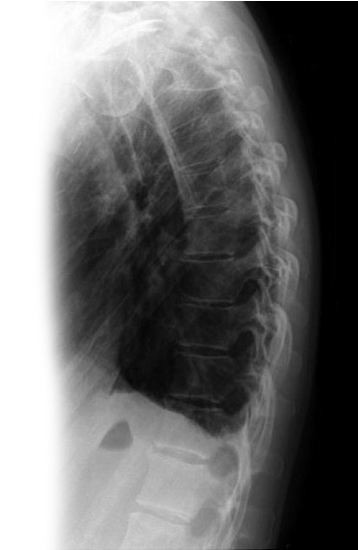

1. Рентгенография органов грудной клетки в 2-х проекциях - скрининговое исследование органов грудной клетки, выполняемое в двух проекциях.